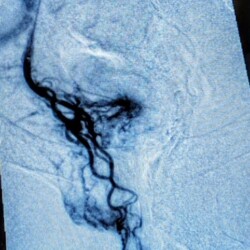

During the procedure a tiny catheter is precisely guided from an artery in the wrist or inguinal region until it reaches the superior rectal artery branches of the inferior mesenteric artery, which supplies blood to the hemorrhoids. Once the catheter is in position, embolic agents, such as small particles or coils, are injected into the artery to block the blood flow to the hemorrhoids. By blocking the blood supply to the hemorrhoidal tissue, the hemorrhoids shrink and eventually resolve. The procedure is typically performed under moderate sedation with the patient asleep. This procedure is generally considered a safe and effective treatment option for symptomatic hemorrhoids, offering a shorter recovery time and potentially fewer complications compared to traditional surgery.